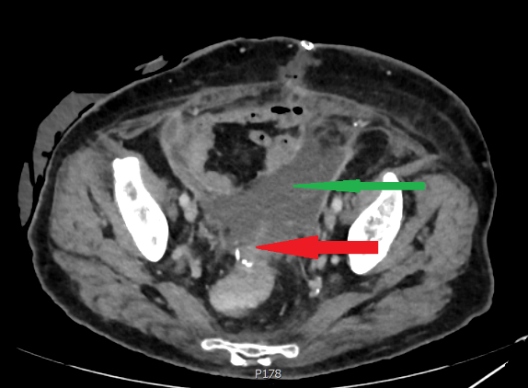

Σχήμα 5 . Η αξονική τομογραφία έδειξε μια οπισθοπεριτοναϊκή μάζα που περιβάλλει τον αριστερό οσφυϊκό ουρητήρα και προκαλεί ουρητηρο-υδρονέφρωση: Η βλάβη αυτή υποδηλώνει υποτροπή . ( Ευγενική παραχώρηση Δρ. Β. Πενόπουλος ) .